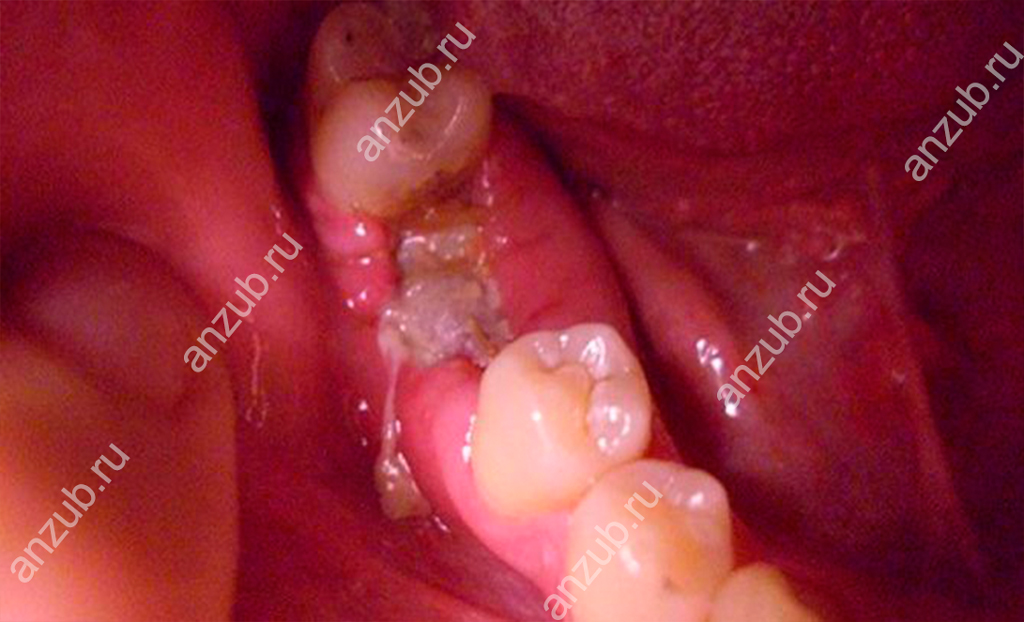

2. Зуб удален частично

При определенных обстоятельствах (неправильных действиях врача, сложной операции и прочих) в лунке могут остаться частицы эмали или даже целые корни. В итоге это приводит к воспалению и образованию гноя. Кроме осколков в ранку могут попасть кусочки твердого бактериального налета как с удаляемой единицы, так и с соседних.

3. Осложнения при удалении зуба мудрости

Третий моляр или «восьмерка» – источник мучений многих пациентов. Прорезывание этой единицы часто сопровождается трудностями: она может быть неправильно расположена, расти не в том направлении, быть в полуразрушенном состоянии или повреждена кариесом и т.д. Поэтому практически во всех случаях зуб мудрости рекомендуют удалять. На его месте остается глубокая ранка, часто требующая наложения швов, приема лекарственных средств, тщательного ухода. Проникновение в нее бактерий грозит нагноением десны.